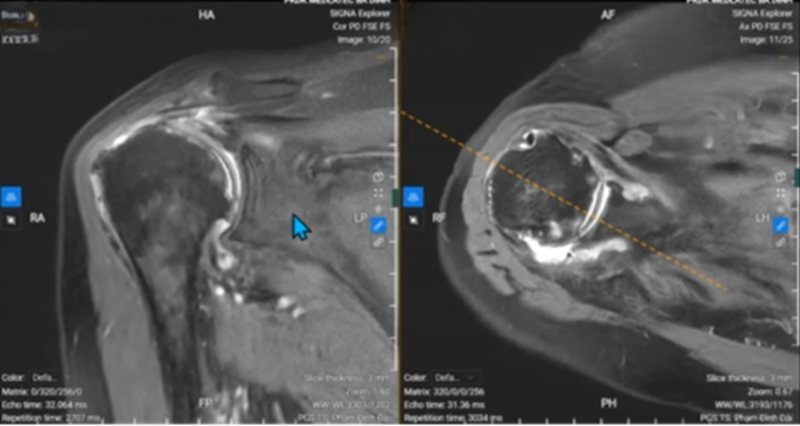

| Tổn thương của bệnh nhân. |

Qua khám lâm sàng, bà H. được chẩn đoán ban đầu là viêm quanh khớp vai, với tình trạng cứng khớp, khó vận động ở hầu hết các động tác, kèm nhiều điểm đau quanh khớp khi ấn. Để đánh giá chính xác mức độ tổn thương, bác sỹ chỉ định chụp cộng hưởng từ (MRI).

Kết quả cho thấy khớp vai của bệnh nhân có nhiều tổn thương nghiêm trọng: thoái hóa nặng, mất hoàn hệ thống sụn đầu xương cánh tay, gần như dính khớp, bong sụn viền ổ chảo, tụ dịch khớp vai và thoái hóa khớp vai.